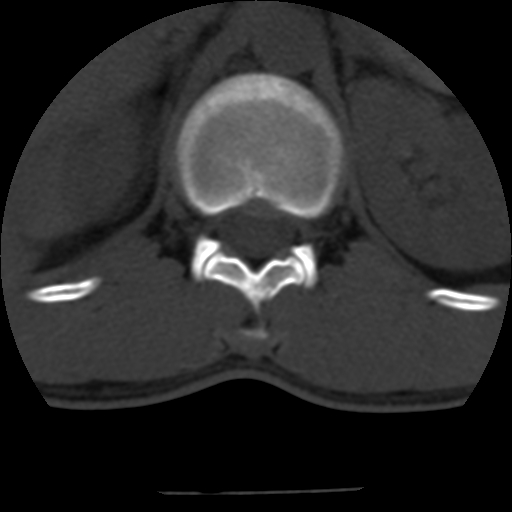

男,31岁,从6米高处坠落伤两天,腰背部疼痛,临床要求ct扫描胸10-腰1。请大家帮忙看看骨质有问题吗?

t12、l1锥体前缘轻度楔形变,平扫示椎体前缘骨小梁欠规整,第9幅图示椎体前缘骨质不连续,结合外伤史考虑椎体轻度压缩骨折。

楼主扫描层厚可能较大,每个椎体只有三个层面.

从所示层面分析,无明确骨折征象,象类似病人我个人会建议mri除外骨挫伤.

从上查骨窗第九片椎体前缘皮质显示断裂.压缩骨折?